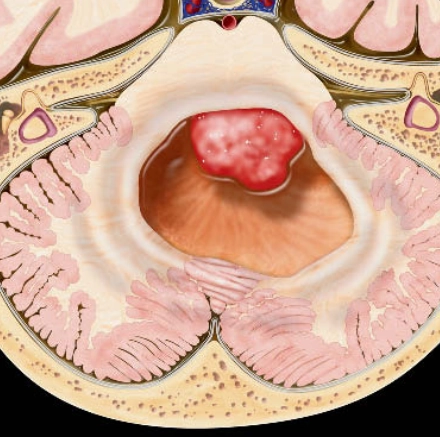

U nguyên tủy bào (Medulloblastoma)

16/03/2026